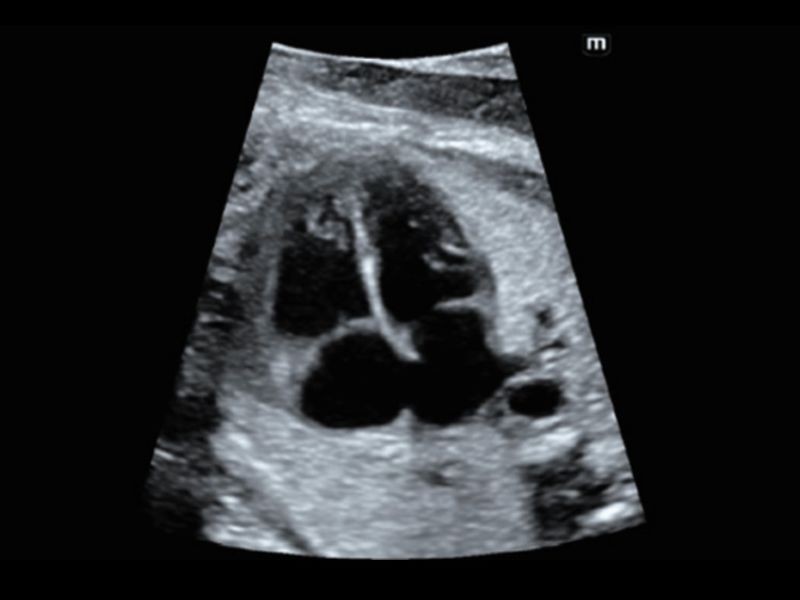

Estudo de folículo inteligente para fertilização in vitro - Smart FLC

O Smart FLC detecta automaticamente o número de folículos e calcula o volume de cada um a partir de uma imagem 3D do volume ovariano, garantindo uma avaliação precisa dos folículos, o que é essencial para exames de fertilização in vitro.